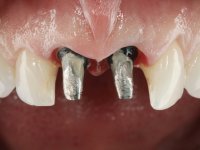

O tratamento iniciou-se com a confeção de moldeiras transparentes em silicone para aplicação de peróxido de carbamida a 16%. Os espaçadores colocados na superfície vestibular foram cuidadosamente preparados em resina nos modelos de gesso. O tratamento foi feito aplicando o produto 2 horas por dia durante 8 dias. Após o branqueamento esperamos 4 semanas e iniciamos o tratamento prostodôntico. Foi realizada uma pré-impressão em silicone para confeção de uma ponte provisória com resina composta de polimerização dual. Em seguida iniciamos a remoção das coroas. Foi feito um corte vertical na zona média da coroa até encontrar a superfície do espigão falso coto fundido. No bordo incisal também foi realizado o mesmo corte. Em seguida com um luxador fino foi feita a separação das partes distais das coroas. Para a remoção das partes mesiais foi feito um corte na linha média abrangendo ambas as coroas. No final da remoção atraumática das coroas antigas os cotos foram re -preparados. Na re-preparação dos cotos a linha de acabamento foi colocada a nível intra-sulcular. Na mesma consulta foi feita a impressão definitiva. O afastamento gengival foi realizado com a técnica da pasta de caolino comprimida pela ponte provisória.  A impressão foi feita pela técnica de dupla mistura com dupla viscosidade com silicone de presa rápida. No laboratório foram confecionadas 2 coroas com infraestrutura em Zr sendo revestidas a cerâmica. No sentido de evitar aparência de coroas “muito altas” foi aumentado ligeiramente o diâmetro mesio-distal sobrepondo-se ligeiramente aos dentes adjacentes. A ponte provisória foi removida os cotos foram polidos e as coroas foram colocadas para verificação final. Confirmado o seu ajuste e aprovadas pela paciente foram cimentadas definitivamente com cimento de ionómero de vidro reforçado com resina.